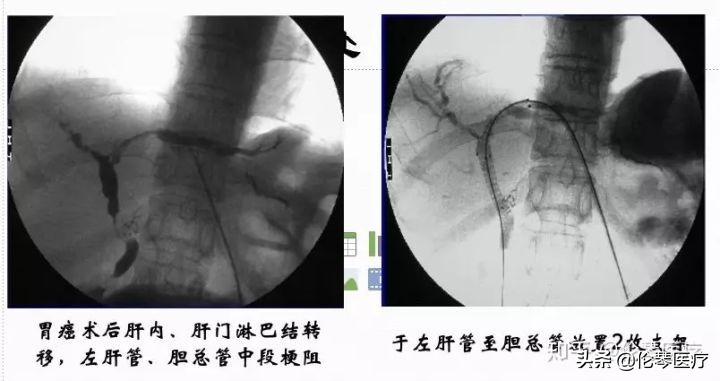

这是一个典型的病例,胃癌术后肝门淋巴结转移导致的梗阻,主要是左肝管和总胆管的中段阻塞。我们放了两枚支架,左肝管和胆总管分别放一个支架。